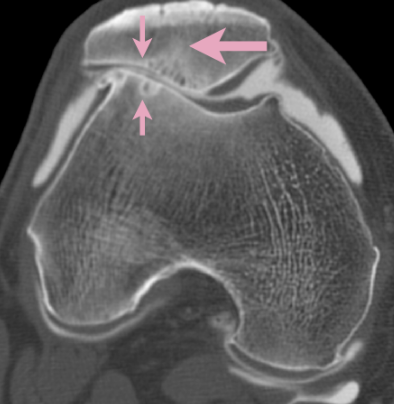

Diagnostic du genou

Le diagnostic de l'arthrose fémoro patellaire est posé sur la base des symptômes cliniques et confirmé par des examens d'imagerie tels que la radiographie, qui montre l'amincissement du cartilage et les éventuelles formations osseuses (ostéophytes).